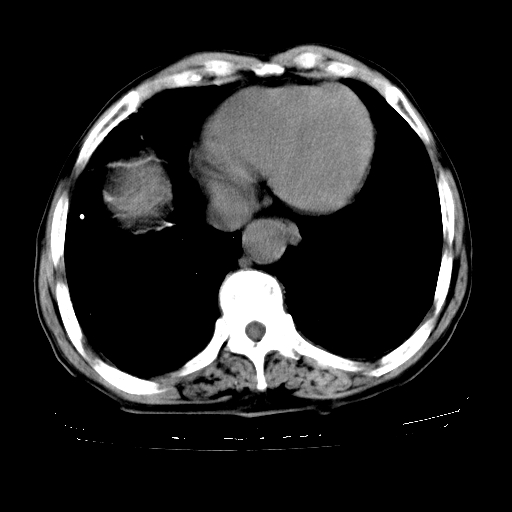

男,72岁,反复咳嗽、憋气一年余,有15年的煤矿井下工作史。

1、双肺中上叶结节影结合病史考虑巨块型矽肺结节。

2、慢支炎并肺气肿

3、双下肺纤维化灶并左下肺局限性肺气肿。

支持 尘肺,肺心病?-------15年的煤矿井下工作史,双上肺叫对称的片团结节影,内见斑状钙化,边缘见粗长毛刺影,肺纹理混乱,可见网状及磨玻璃样影,肺门纵膈见多个淋巴结钙化